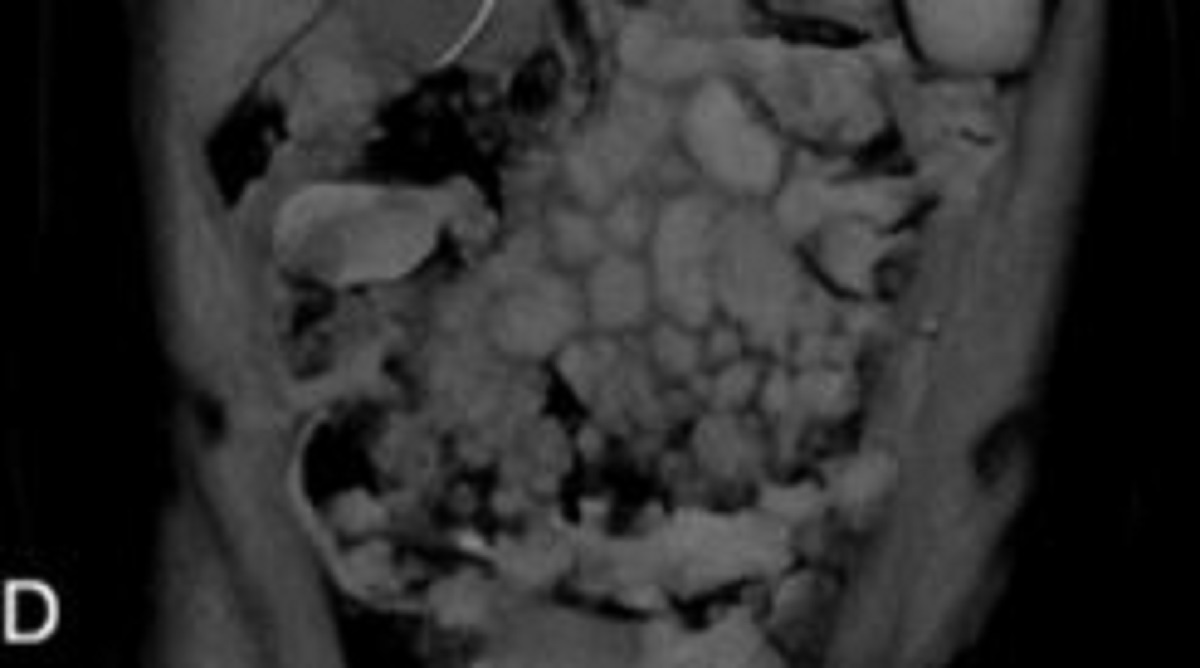

¸ß½ÃÄÚ È£¼¼ ¿¤·¹¿ìÅ׸®¿À °ï»ì·¹½º´ëº´¿ø ³»°ú ÀÇ·áÁø¿¡ µû¸£¸é, 23¼¼ ¿©¼ºÀÌ º¹Å롤ºóÇ÷ µî°ú °°Àº Àü½Å Áõ»óÀÌ ³ªÅ¸³ª ÀÔ¿ø ÈÄ °Ë»ç¸¦ ¹Þ¾Ò´Ù. ±× °á°ú, ¿©¼ºÀº ¹öŶ¸²ÇÁÁ¾À» Áø´Ü¹Þ¾Ò´Ù.

¹öŶ¸²ÇÁÁ¾Àº ¹éÇ÷±¸ Áß B¸²ÇÁ±¸¿¡¼ ±âÀÎÇÏ´Â Ç÷¾×¾ÏÀ¸·Î, ¸²ÇÁ°è¿¡ ¹ß»ýÇÑ´Ù. ¹öŶ¸²ÇÁÁ¾Àº ºñÈ£ÁöŲ ¸²ÇÁÁ¾¿¡ ¼ÓÇØ¼ ºü¸£°Ô ÁøÇàµÇ´Â °ø°ÝÇü ¸²ÇÁÁ¾ÀÌ´Ù. ¸²ÇÁÁ¾Àº ¹éÇ÷±¸ Áß ÇϳªÀÎ ¸²ÇÁ±¸°¡ ¾Ç¼º ¼¼Æ÷·Î º¯ÇÑ Á¾¾çÀÌ´Ù. °ñ¼ö³ª Ç÷°ü, º¹ºÎ ±â°ü µîÀ¸·Î ħ¹üÇÒ ¶§°¡ ¸¹¾Æ ħ¹ü ºÎÀ§¿¡ µû¶ó µÎÅë, ±¸Åä, º¹ºÎ ºñ´ë°¡ ³ªÅ¸³´Ù.

¿©¼º¿¡°Ô´Â ¿øÀÎÀ» ¾Ë ¼ö ¾ø´Â Ȳ´Þ, ÃéÀå¿°, Æó Áúȯ µîÀÇ Áõ»óµµ ÇÔ²² ³ªÅ¸³µ´Ù. ÀÌÈÄ Ä¡·á °úÁ¤¿¡¼ 15cm ±æÀÌÀÇ È¸ÃæÀÌ ¹èÃâµÆ°í, ´ëº¯ °Ë»ç·Î È¸Ãæ °¨¿°À» µÚ´Ê°Ô È®ÀÎÇß´Ù. Ç×±â»ýÃæ Ä¡·á¿¡µµ ºÒ±¸ÇÏ°í ¿©¼ºÀº ³Ä¡¼º ÆÐÇ÷Áõ ¼îÅ©·Î °á±¹ »ç¸ÁÇß´Ù.